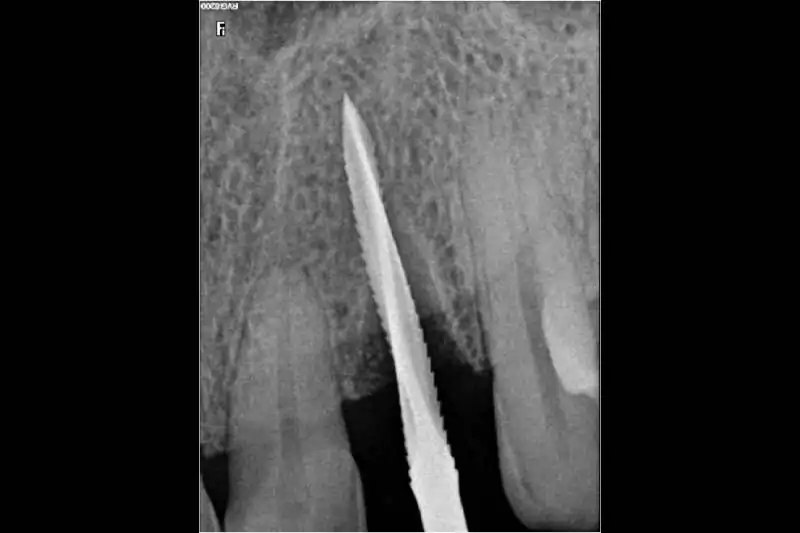

After a thorough clinical examination of your jaw bone, the Best dentist in Pune at Smilex confirms the available jaw bone by CBCT scan or X-rays. The doctors then administer a very small cut in the gums under local anesthesia. A painless drill sequence leads to the final drill position, after which the dental implants in Pune are placed in the bone. Gums are then placed back in their original position. A single implant procedure takes up to 45 mins to be done.

If you think you need reconstruction, see us for a comprehensive examination. We will examine your mouth to determine the extent of the problem and the treatment options that can be used to correct it. The examination process requires records of your mouth such as xrays ,digital opg ,3D CBCT scan ,intra-oral digital scan. We may also have consultations with specialists (periodontist, orthodontist, oral surgeon) in order to develop a treatment plan that is best for you.